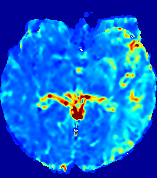

LesionRefer to captionRefer to captionRefer to captionRefer to captionRefer to captionRefer to caption𝐕rgbsubscript𝐕𝑟𝑔𝑏{\bf{V}}_{rgb}Refer to captionRefer to captionRefer to captionRefer to captionRefer to captionRefer to caption𝐕2subscriptnorm𝐕2{\|\bf{V}}\|_{2}Refer to captionRefer to captionRefer to captionRefer to captionRefer to captionRefer to captionRefer to caption3.53.53.52.82.82.82.12.12.11.41.41.40.70.70.70.00.00.0(mm/s)𝑚𝑚𝑠(mm/s)D𝐷DRefer to captionRefer to captionRefer to captionRefer to captionRefer to captionRefer to captionRefer to caption0.0200.0200.0200.0160.0160.0160.0120.0120.0120.0080.0080.0080.0040.0040.0040.0000.0000.000(mm2/s)𝑚superscript𝑚2𝑠(mm^{2}/s)Slice #1Slice #2Slice #3Slice #4Slice #5Slice #6

Figure 4: PIANO feature maps for another patient in the ISLES 2017 training set, where the lesion is located in the right hemisphere. Top row: segmented stroke lesion region (white) on different slices. The corresponding slices for the PIANO feature maps are shown in the following rows.

For a better insight into an estimated velocity field 𝐕𝐕{\bf{V}} and diffusion field 𝐃𝐃{\bf{D}}, we compute the following maps: (1) 𝐕rgbsubscript𝐕𝑟𝑔𝑏{\bf{V}}_{rgb}: Color-coded orientation map of 𝐕=(Vx,Vy,Vz)T𝐕superscriptsuperscript𝑉𝑥superscript𝑉𝑦superscript𝑉𝑧𝑇{\bf{V}}=(V^{x},V^{y},V^{z})^{T}, obtained by normalizing 𝐕𝐕{\bf{V}} to unit length and mapping its 3 components to red, green, blue respectively; (2) 𝐕2subscriptnorm𝐕2\|{\bf{V}}\|_{2}: 222 norm of 𝐕𝐕{\bf{V}}; (3) D𝐷D: scalar field in Eq. 5.

Fig. 3 and Fig. 4 show the PIANO feature maps estimated from two ISLES 2017 patients: all are highly consistent with the lesion in both cases. Details of the blood flow trajectories are revealed in 𝐕rgbsubscript𝐕𝑟𝑔𝑏{\bf{V}}_{rgb} by the ridged patterns and the sharp changes of colors in the unaffected (right) hemisphere, while the flat patterns appearing within the lesion provide little directional information about the velocity and indicate low velocity magnitudes. Velocity magnitudes are more directly visualized via 𝐕2subscriptnorm𝐕2\|{\bf{V}}\|_{2}, from which one can easily locate the lesion where 𝐕2subscriptnorm𝐕2\|{\bf{V}}\|_{2} is low. D𝐷D also indicates lower diffusion values in the lesion, though with less contrast potentially due to the fact that it captures the accumulated effect of CA diffusion at the voxel-level.